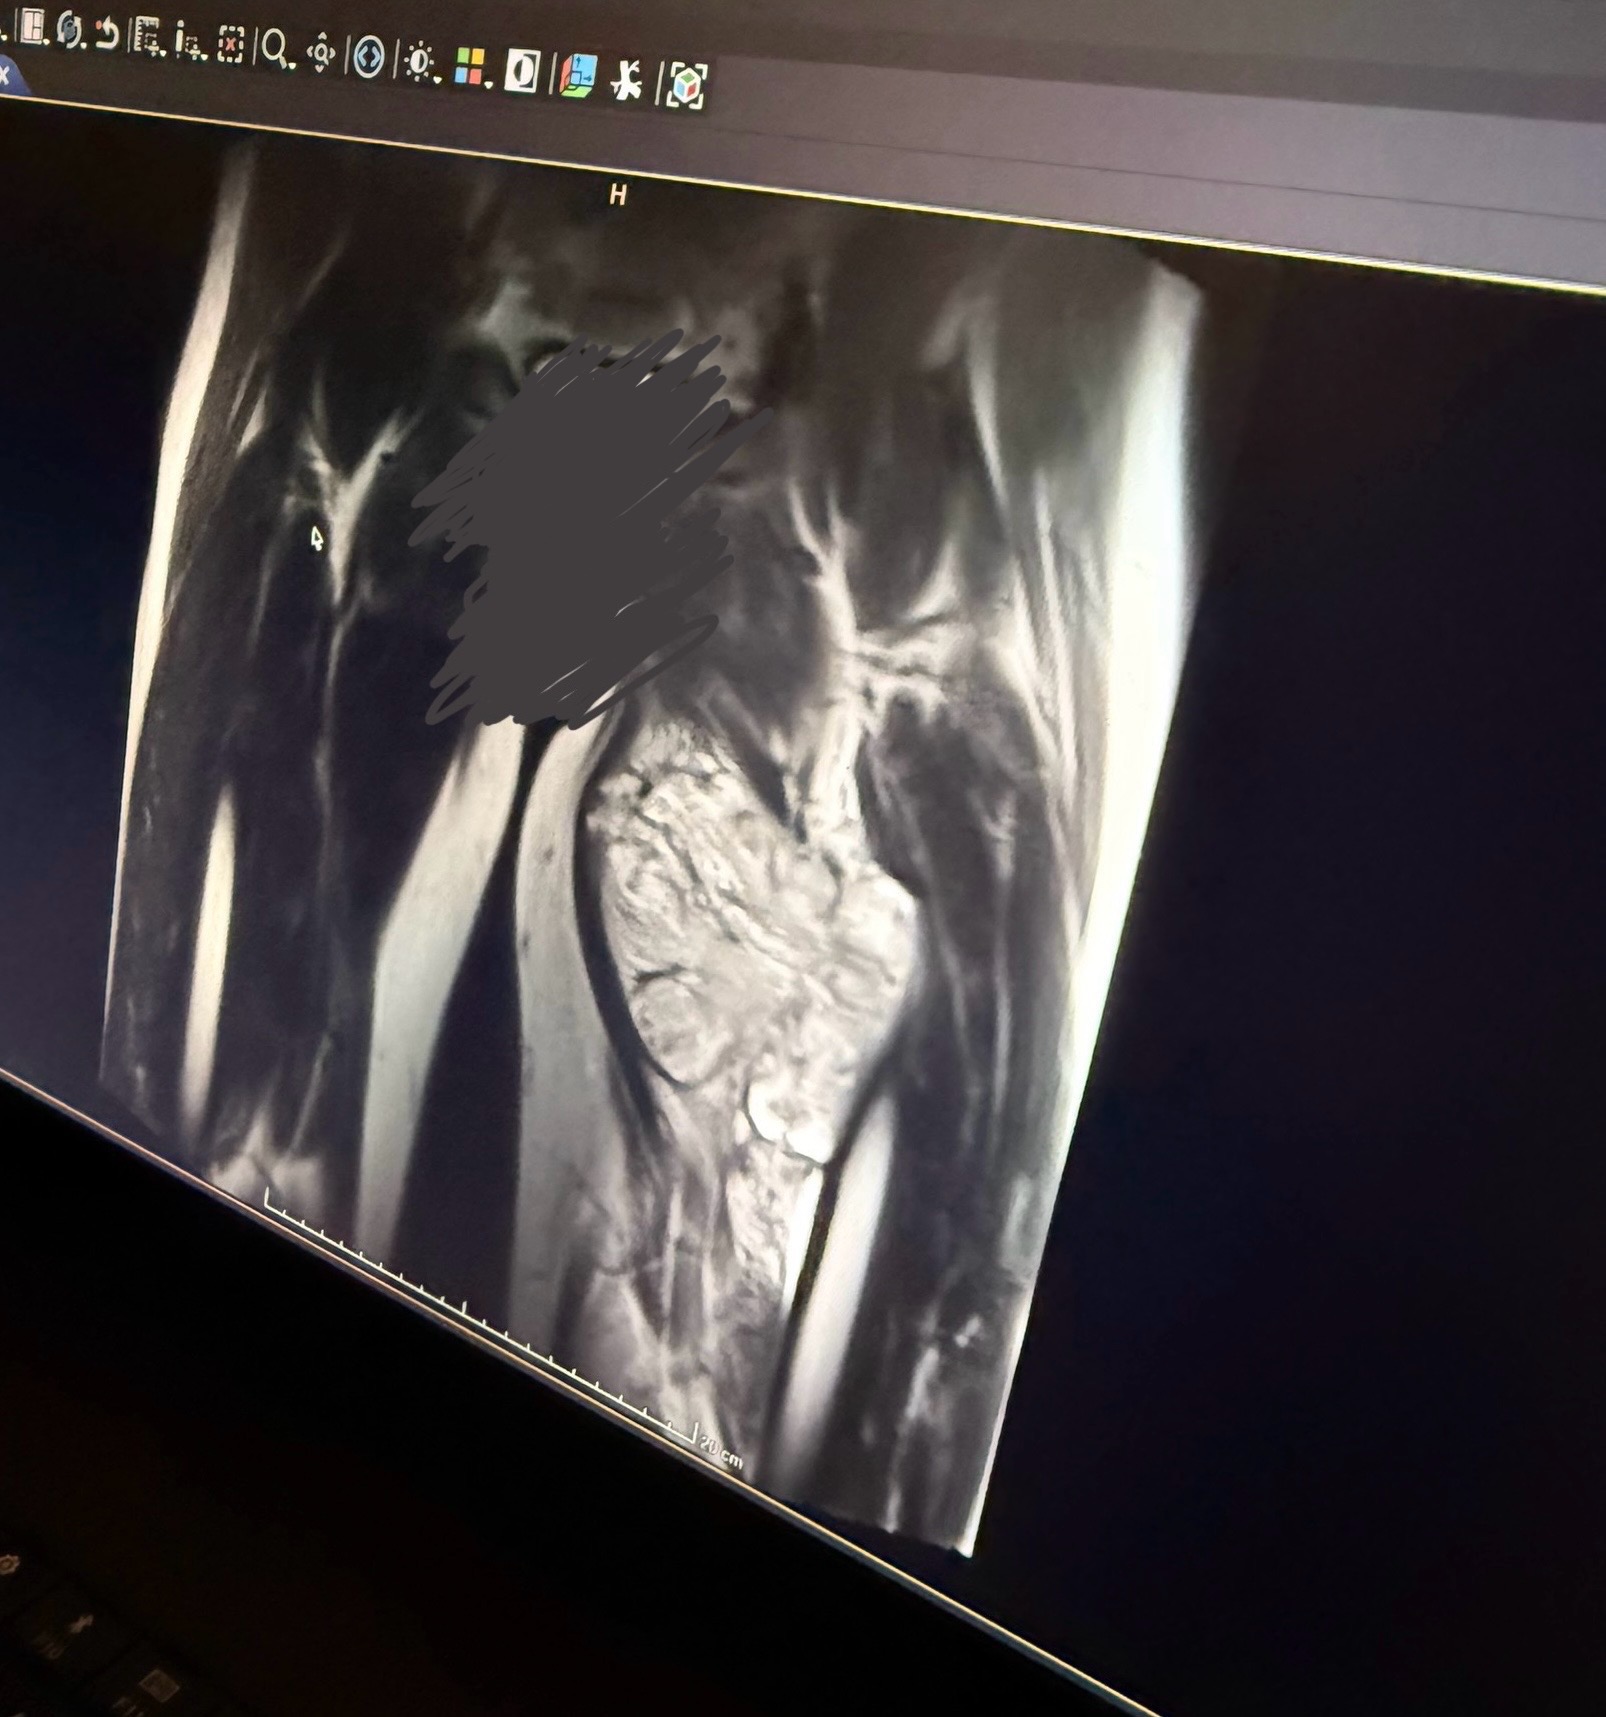

Hi everyone, my name is Aurora and my sweet boyfriend Blake Dore has recently been diagnosed with a Synovial Soft Tissue Sarcoma, a rare form of Cancer found in less than 1% of cancer cases. It is a 12cm tumour growing in his thigh, wrapping around his muscles and artery. It is chemo resistant and can only be treated with radiation and surgery. He will undergo 25+ radiation treatments here in Sudbury and have surgery in Toronto in the weeks following. We are looking for financial support during this time to go toward our travels to Mount Sinai Hospital in Toronto for surgery and recovery. Fertility expenses due to radiation side effects and general health related bills. As a young couple living on our own we are overwhelmed by the potential costs. Anything helps and we appreciate it so much. Thank you.